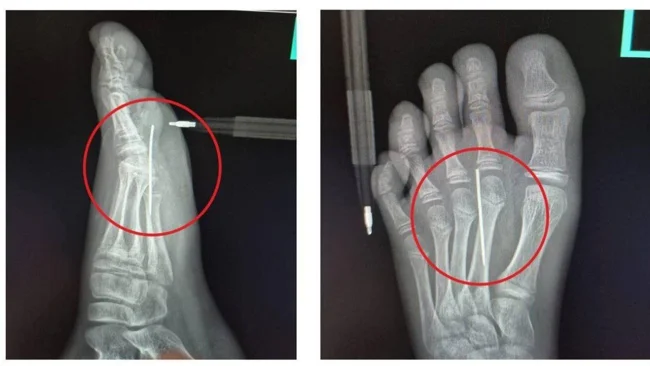

Юного “участника” родителям пришлось отвозить в больницу. Там врачи сделали мальчику рентген и за 3 минуты извлекли посторонний предмет с помощью специального прибора.